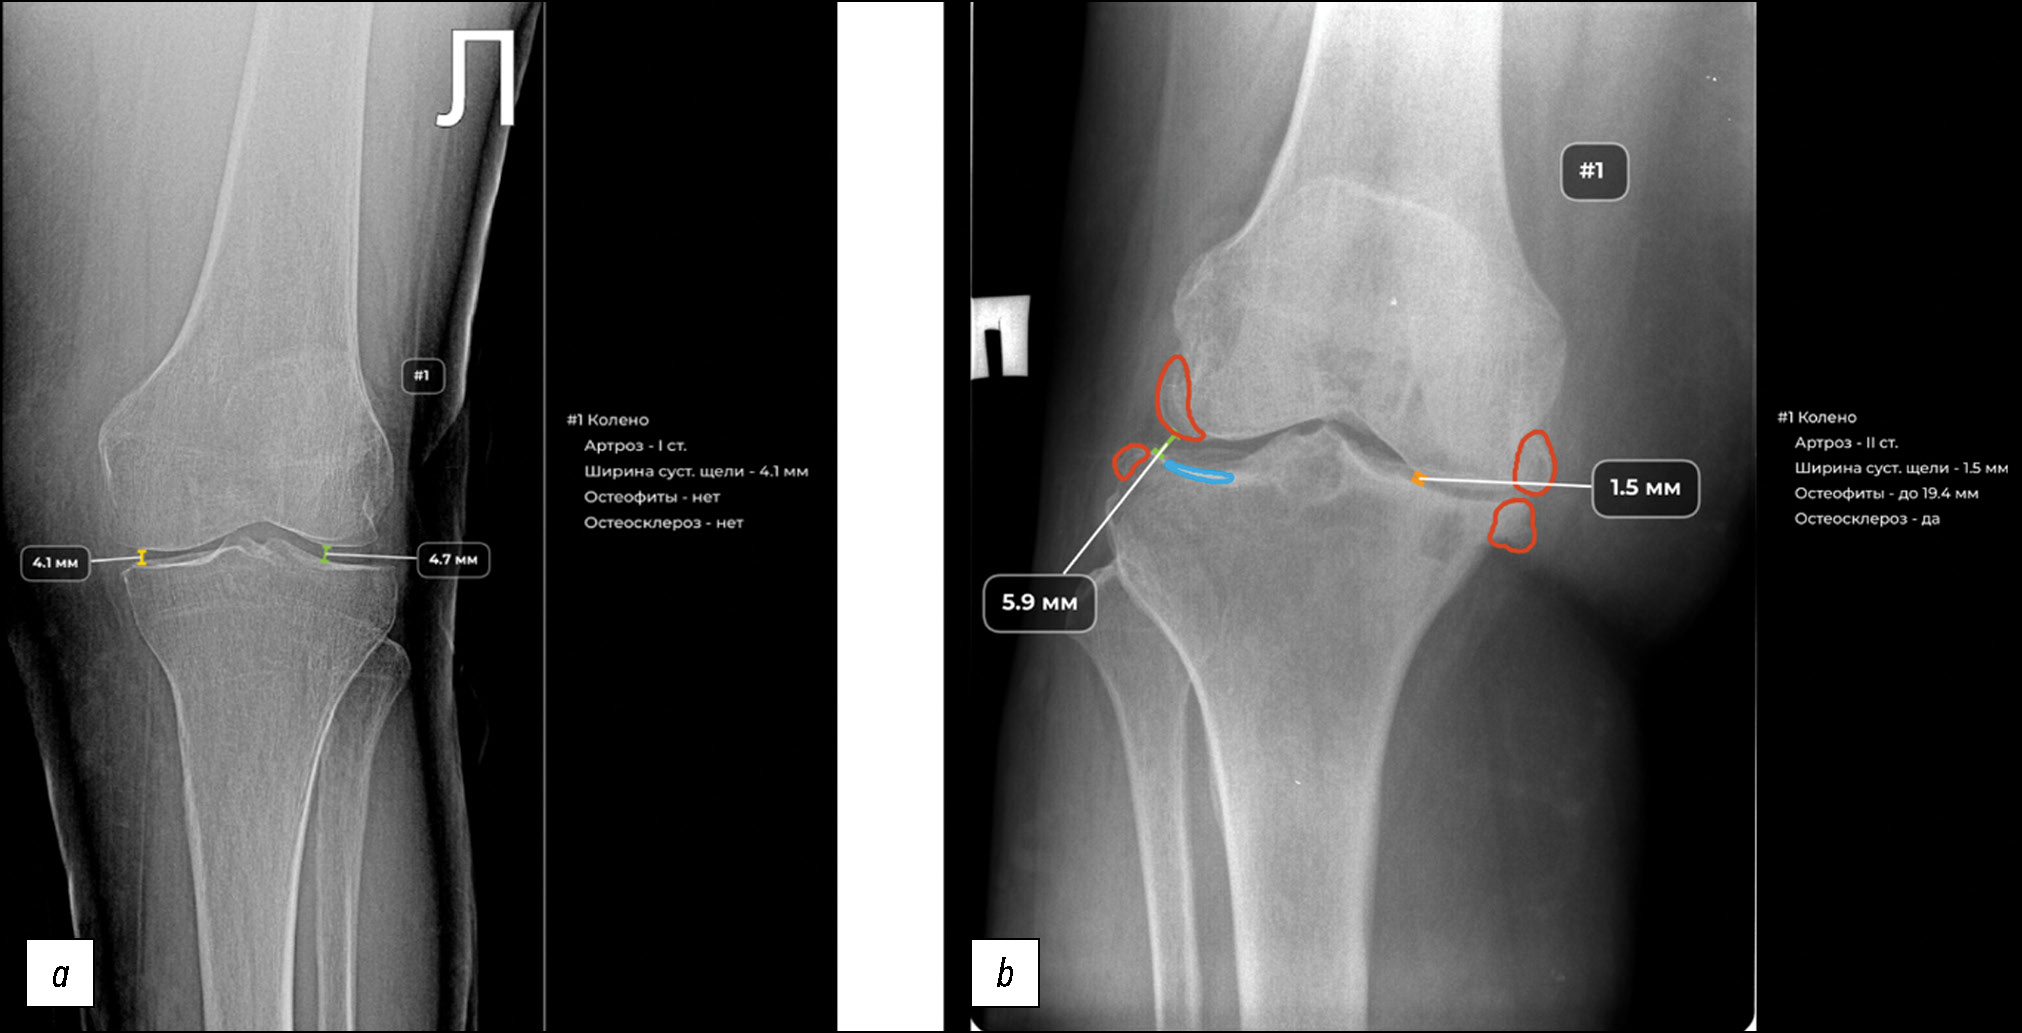

Технически и организационно ИИ-3 и ИИ-4 переведены в промышленный контур ЕРИС ЕМИАС для выполнения автоматизированного анализа реального потока результатов рентгенографии коленного сустава (рис. 2).

Рис. 2. Пример обработки результатов рентгенографии коленного сустава ИИ-сервисом: a — артроз коленного сустава I стадии, b — артроз коленного сустава II стадии.

Fig. 2. Example of knee joint radiographs processing by AI-service: a — knee arthrosis stage I, b — knee arthrosis stage II.

При работе в клинических условиях оба ИИ-сервиса продемонстрировали достаточную техническую надёжность и высокую скорость обработки данных; в подавляющем большинстве случаев автоматизированный анализ результатов рентгенографии выполнялся менее чем за 60 секунд.